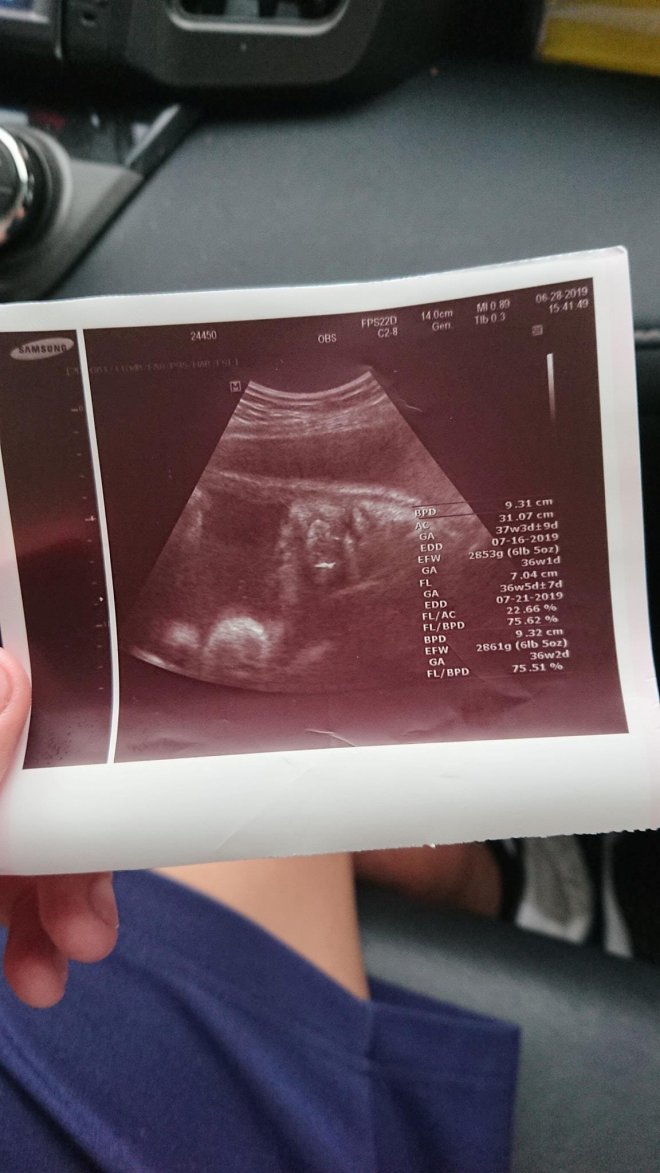

結果醫生說:胎兒是個男孩,已經約37週大,而且預產期大約在7月中。

天呀~37週…37週…37週…這完全是只能選擇生下來了…

7/1 為保險起見,帶著兒子的女朋友到大醫院再檢查一次,

結果醫生說已經開2指,今晚或明天早上就會生了,馬上安排住院待產…